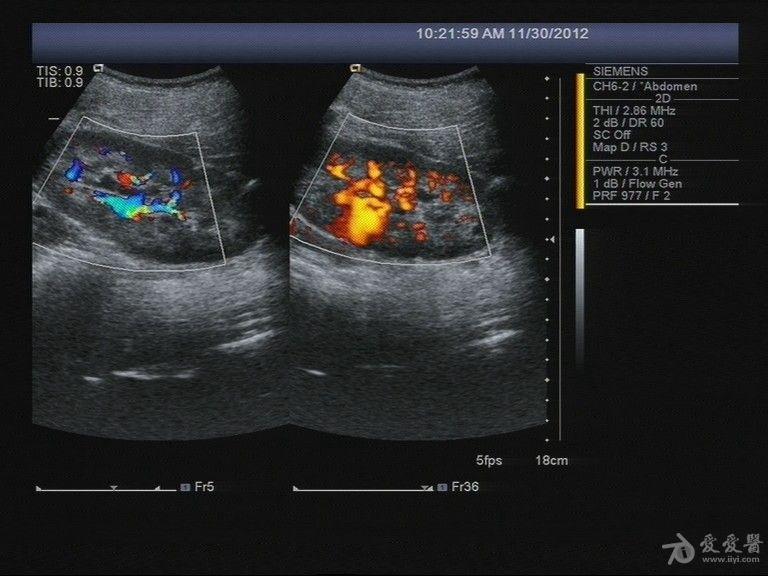

昨天碰到一例怀疑是海绵肾的病例 - 超声医学讨论版 - 爱爱医医学论坛

图片尺寸768x576